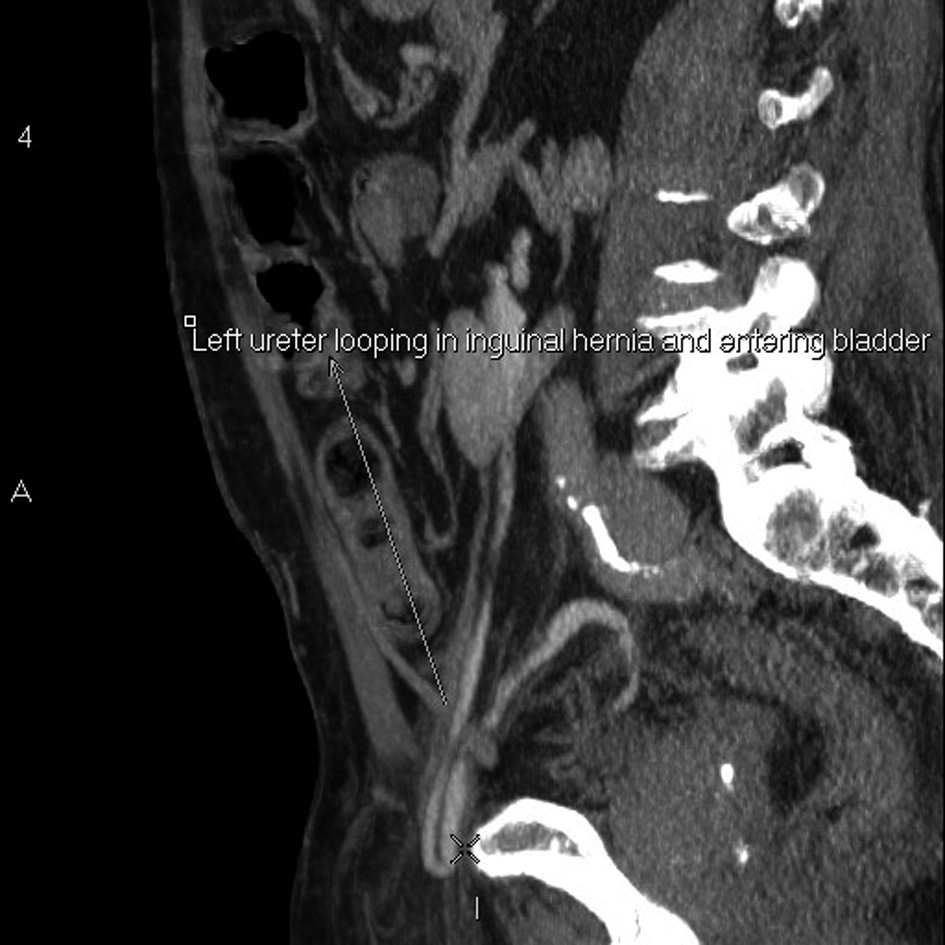

An 83-year old male with benign prostatic enlargement (BPE) presented with acute urinary retention with renal failure, constipation and weight loss. On examination, he had large bilateral asymptomatic inguinal herniae. Following catheterisation and medical renal failure management, a contrast-enhanced CT scan was performed to investigate his constitutional symptoms. An incidental finding was partial left ureteral duplication, and urography revealed that the distal part of one limb looped into the left inguinal hernia before inserting into the bladder (Fig. 1-4). The patient’s renal function normalised with catheterisation, which was definitive management of his BPE due to medical co-morbidities.

![]() Click for large image | Figure 2. Sagittal reconstruction of abdominal and pelvic CT urogram demonstrating one limb of the partially-duplicated left ureter entering and leaving the inguinal canal. |